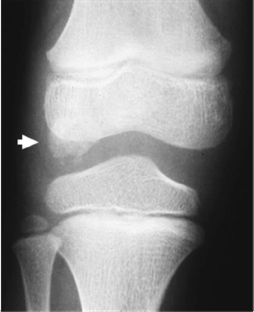

We found that, unlike in osteochondroma, DEH was radiographically not clearly separable from the underlying or host bone with preserved cortical bone and marrow continuity. The finding in the talus distinguished DEH from (osteochondroma-like) parosteal osteosarcoma, in which a radiolucent demarcation line clearly separated the tumor from the host bone. The DEH mass had a well-defined low to intermediate signal intensity on T1-weighted images and an intermediate to high signal intensity on T2-weighted images, with irregularity of the articular surface. Simple excision was performed in all patients. The excision was complete in six patients and incomplete in two patients whose lesions was juxta-articular in the ankle and articular in the knee, respectively. The residual mass slowly absorbed and vanished, resulting in mild flaring of the affected portion of the epiphysis. No local recurrence or complication was seen in any of the eight patients.

Although the radiographic signs of DEH are characteristic, (osteochondroma-like) parosteal osteosarcoma should be differentiated from DEH when there is a radiolucent separation line between the mass and host bone in the talus. Simple excision was effective in the management of DEH if the deformity was not complicated. Incompletely excised masses resolved and vanished with time.